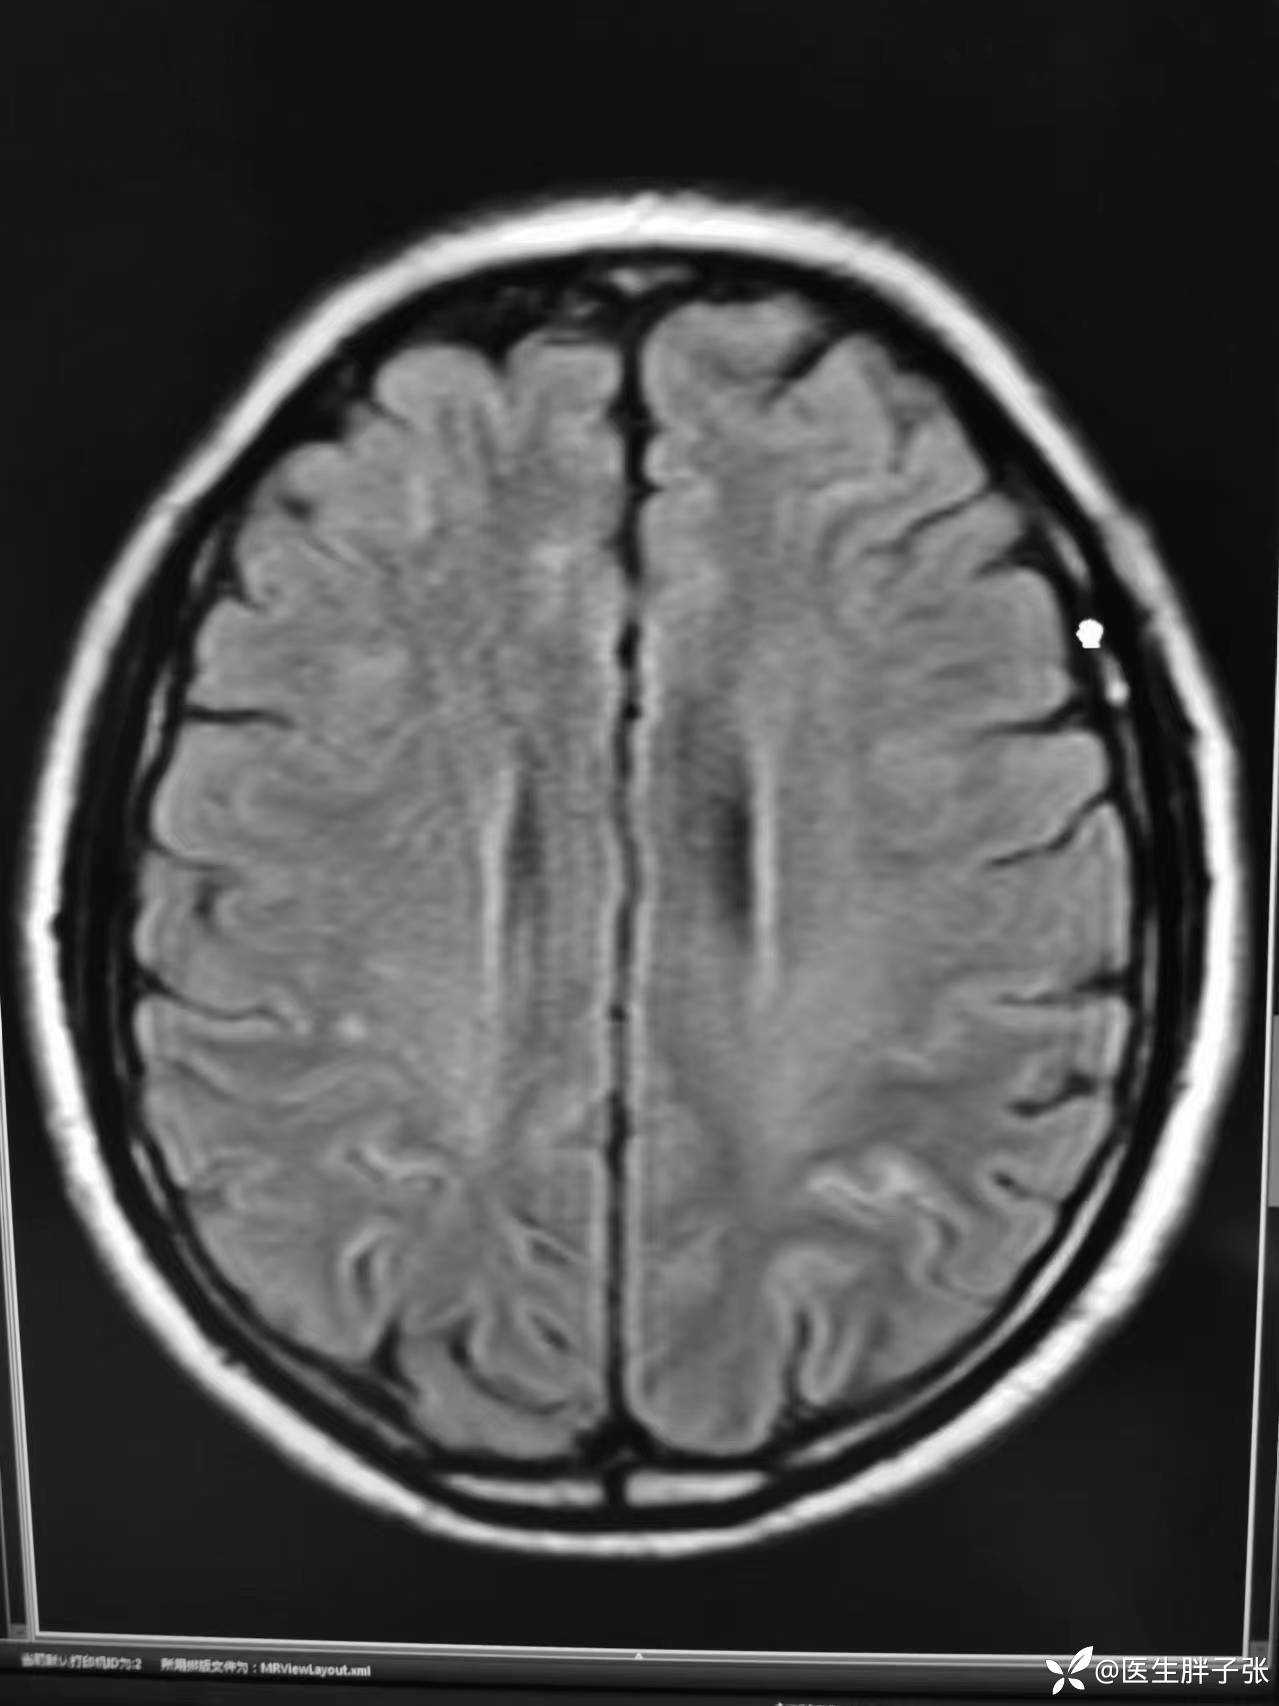

再次查看核磁,考虑患者左侧顶枕叶及右侧枕叶脑组织存在混杂信号。

复查头颅CT,值班医生认为仍存在脑肿胀

患者头痛明显,恶心呕吐,诉双眼视物不清,存在视幻觉,自诉看见有人在自己右侧平躺着,诉看见医生衣服上有树叶飘落。双耳听力减退,记忆力减退,不能回忆昨日发生事情,反应迟钝。